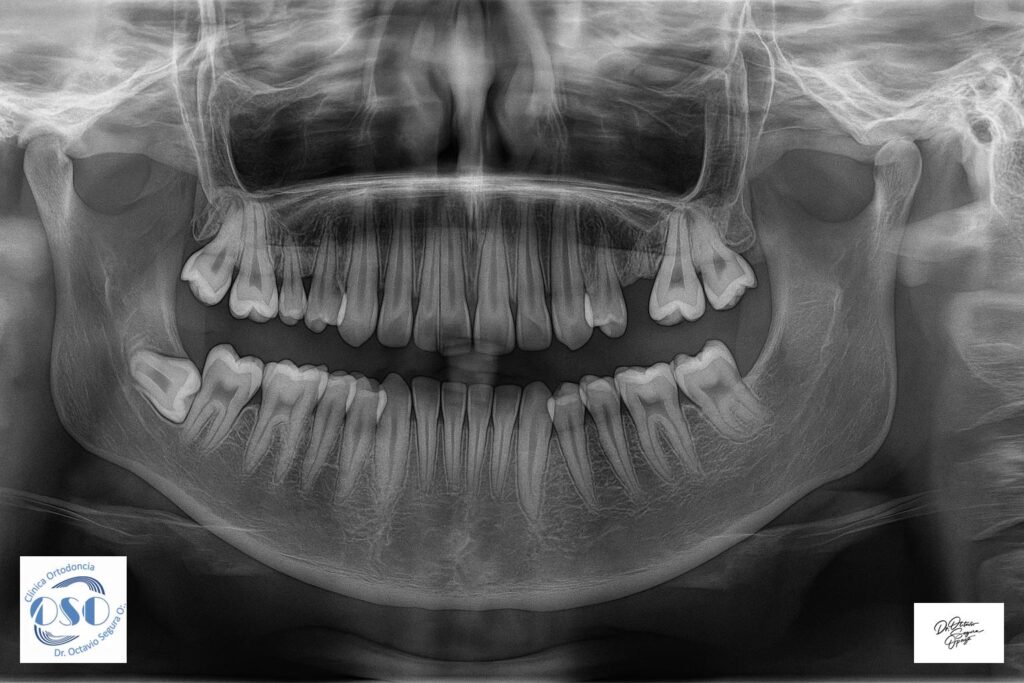

Clínica Ortodoncia Doctor Octavio Segura O.: Información Relevante Ortodoncia en Castro: Todo lo que debes saber para mejorar tu sonrisa ¿Buscas un tratamiento de ortodoncia en Castro que sea seguro, profesional y con resultados garantizados? En este artículo te contamos todo lo que necesitas saber ... Leer más → Implantes cortos en sector posterior de maxilar inferior Leer documento sobre implantes cortos (Short) ¿Es necesaria la exodoncia preventiva de treceros Molares? ¿Son los implantes para toda la vida? Enfermedad Periodontal y Vitamina D